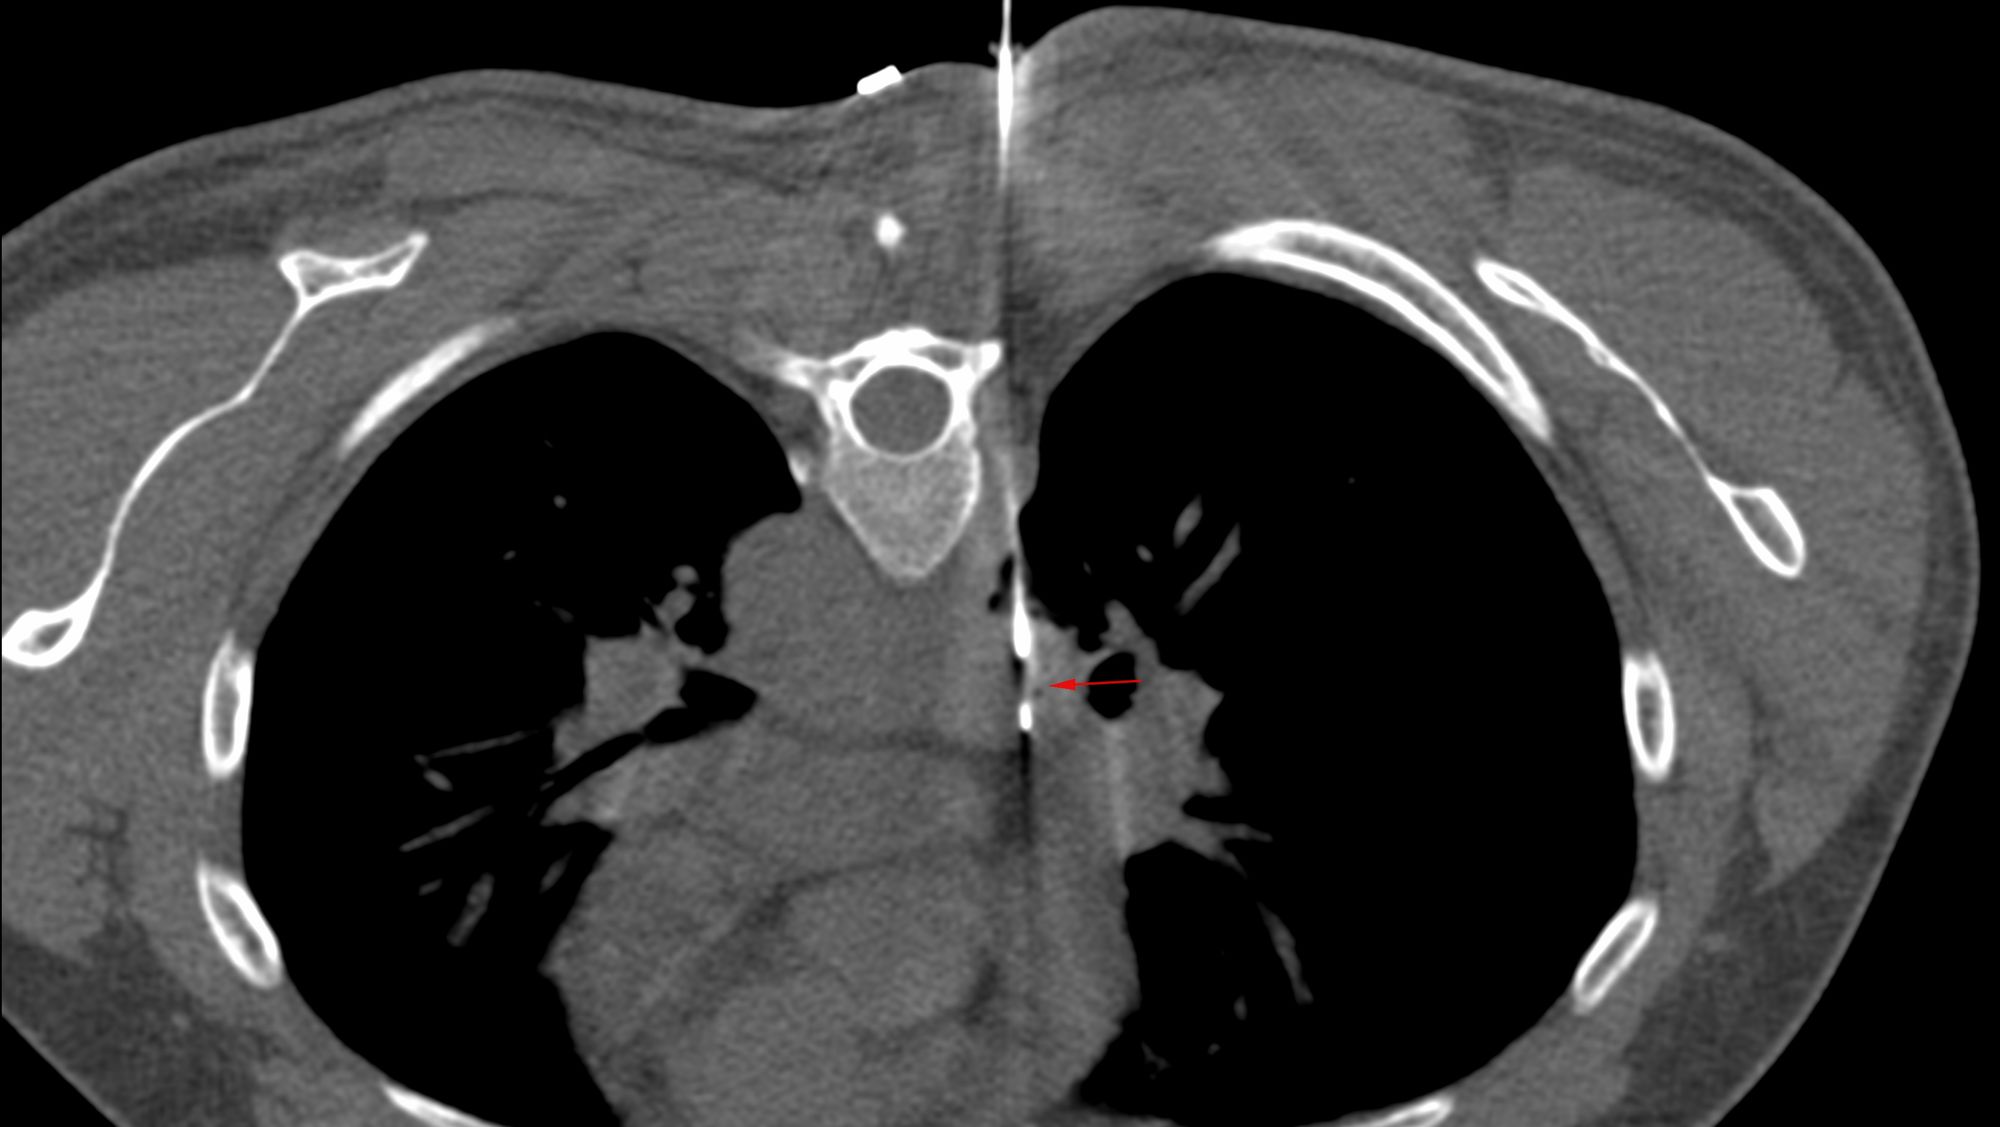

Case 31: Subcarinal Node Biopsy - Transpulmonary Approach

Bhavin Jankharia - 10 May 2021